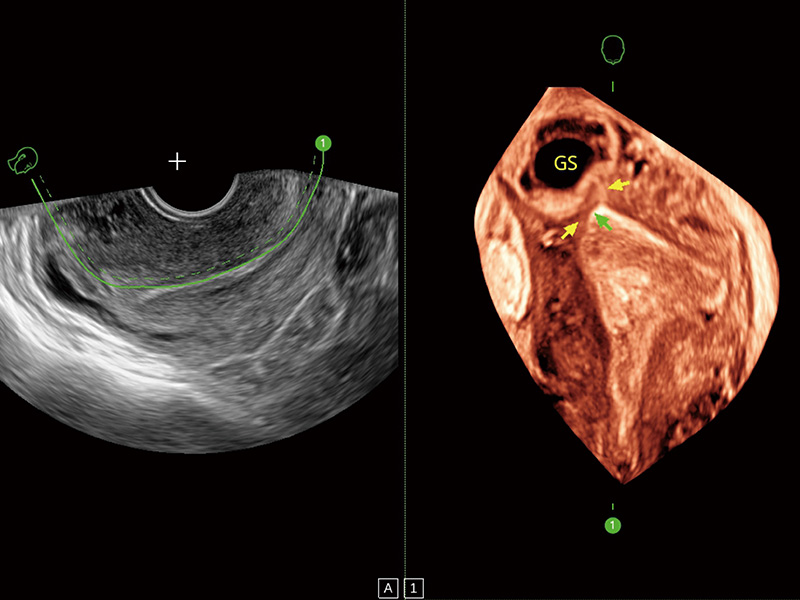

中央型宫腔粘连